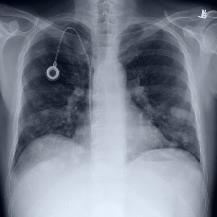

Thoracic disease detection from chest radiographs using deep learning methods has been an active area of research in the last decade. Most previous methods attempt to focus on the diseased organs of the image by identifying spatial regions responsible for significant contributions to the model's prediction. In contrast, expert radiologists first locate the prominent anatomical structures before determining if those regions are anomalous. Therefore, integrating anatomical knowledge within deep learning models could bring substantial improvement in automatic disease classification. This work proposes an anatomy-aware attention-based architecture named Anatomy X-Net, that prioritizes the spatial features guided by the pre-identified anatomy regions. We leverage a semi-supervised learning method using the JSRT dataset containing organ-level annotation to obtain the anatomical segmentation masks (for lungs and heart) for the NIH and CheXpert datasets. The proposed Anatomy X-Net uses the pre-trained DenseNet-121 as the backbone network with two corresponding structured modules, the Anatomy Aware Attention (AAA) and Probabilistic Weighted Average Pooling (PWAP), in a cohesive framework for anatomical attention learning. Our proposed method sets new state-of-the-art performance on the official NIH test set with an AUC score of 0.8439, proving the efficacy of utilizing the anatomy segmentation knowledge to improve the thoracic disease classification. Furthermore, the Anatomy X-Net yields an averaged AUC of 0.9020 on the Stanford CheXpert dataset, improving on existing methods that demonstrate the generalizability of the proposed framework.